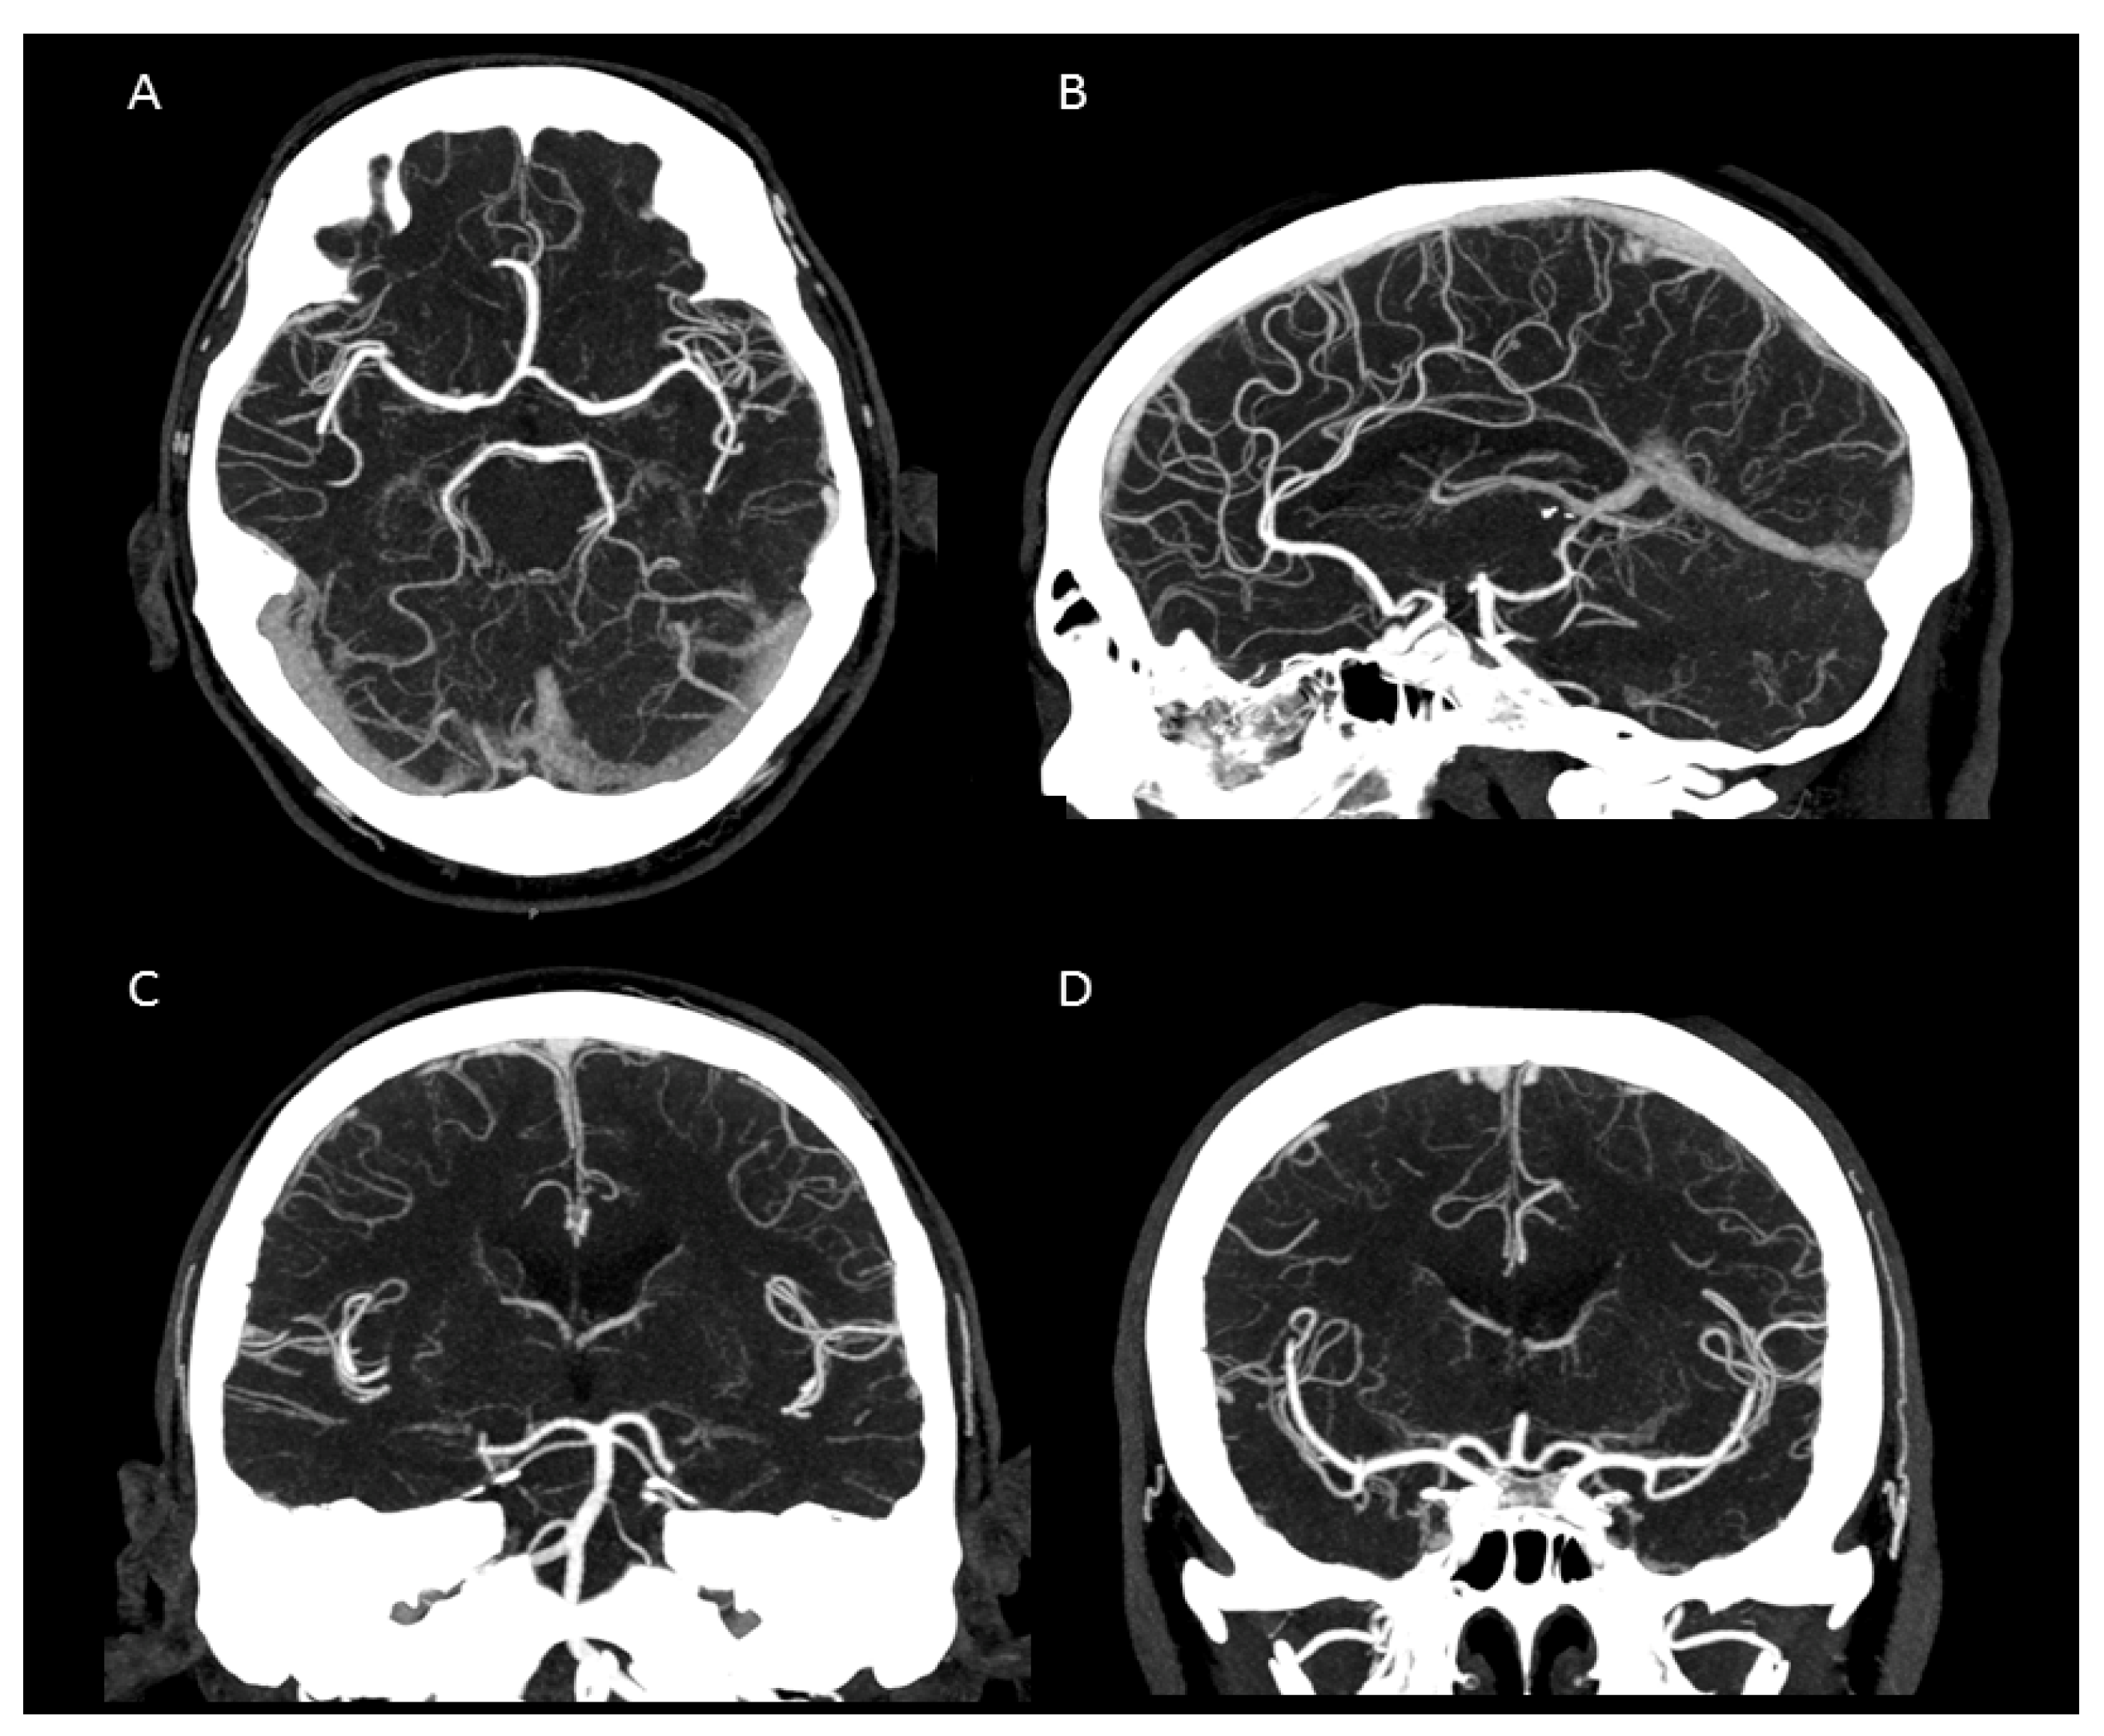

Figure 3.

Maximum intensity projection of an intracranial UHR-CTA. (A) axial plane. (B) sagittal plane. (C,D) coronal plane. Note the clear traceability/visualization of the circle of Willis and even the small peripheral vessel branches.

In summary, the subjective analysis of all images showed excellent results for the applied qualitative parameters such as overall image quality, overall contrast noise and artefacts, the latter focusing on streaks within the posterior fossa. A high-rated vessel contrast and delineation could also be observed, which were not only limited to the large cerebral vessels but also appeared in the smaller vessel sections, especially in the deep cerebral perforators (e.g., lenticulostriate arteries). Patient examples are given in Figure 2, Figure 3, Figure 4 and Figure 5. Interrater reliability was ascertained by applying Cohen’s kappa coefficient and showed a fair agreement (k = 0.26).

We were able to show that excellent image qualities were generated even though radiation exposure could be kept at explicitly moderate levels [10]. In addition, the occurrence of Hounsfield artefacts that frequently hinder the assessment of the vertebrobasilar system and the brainstem were also considerably low, enabling an advanced image interpretability. Both quantitative and qualitative evaluation of the UHR-CTAs confirmed our hypothesis of a highly remarkable improvement in image quality and spatial resolution. In particular, a high vascular contrast and a distinctly defined demarcation of the extracranial as well as the intracranial vessels could be demonstrated. It is noteworthy that even the smallest perforating arteries (e.g., LSA, as shown in Figure 3) vascularizing the deep brain structures become diagnostically accessible by UHR-CTA, which is generally not the case when using conventional CTA.